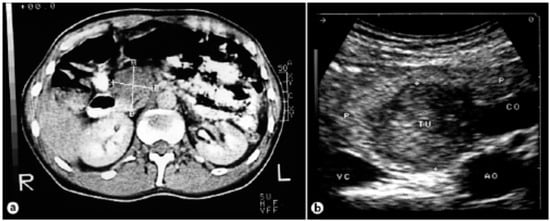

Figure 8.

(a) Computed tomography of the abdomen showing a tumor of the pancreas 4.2 × 3.3 cm in size. (b) Intraoperative ultrasound showing a hypoechogenic tumor [].